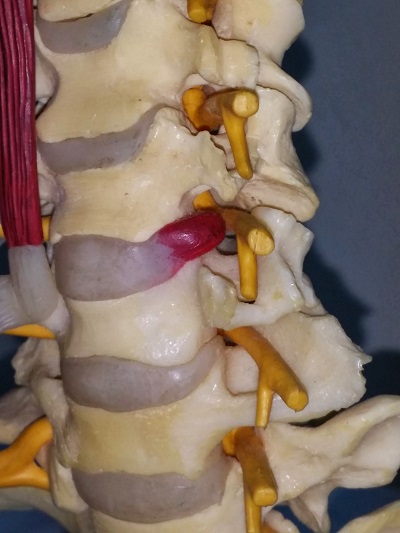

สามารถแบ่งได้ตามช่วงอายุและอุบัติการณ์ของการเกิดอาการปวดต้นคอ ซึ่งสามารถเกิดได้ตั้งแต่อายุ 20 ปีเป็นต้นไป สาเหตุส่วนใหญ่มักเกิดจากการใช้งานไม่ถูกท่า การนั่งทำงานกับคอมพิวเตอร์เป็นระยะเวลานานอย่างต่อเนื่อง การก้มใช้งานมือถือ ทำให้ต้องก้มคอตลอดเวลา ซึ่งส่งผลทำให้กล้ามเนื้อเกิดอาการเกร็งตัว ทำให้เกิดอาการปวดเมื่อยตามบริเวณต้นคอและสะบักทั้ง 2 ข้าง ในบางครั้งที่มีอาการปวดต้นคออย่างรุนแรง อาจจะเกิดเนื่องจากหมอนรองกระดูกต้นคอเคลื่อนออกมากดทับเส้นประสาท ทำให้เกิดอาการบวมและอักเสบของเส้นประสาท นอกจากนี้ตัวหมอนรองกระดูกที่เคลื่อนออกมานั้นจะมีสารที่ทำให้เกิดการอักเสบโดยตรงต่อเส้นประสาท จึงทำให้ผู้ป่วยมีอาการปวดคอร้าวลงแขนเพิ่มมากขึ้น รวมทั้งในบางรายอาจจะมีอาการชา และอ่อนแรงของแขนในข้างที่เส้นประสาทไปกดทับด้วย เมื่ออายุมากขึ้น ส่วนใหญ่ประมาณตั้งแต่ 45 ปีขึ้นไป อาการปวดคอส่วนใหญ่มักเกิดจากกระบวนการเสื่อมของหมอนรองกระดูกและการอักเสบของข้อต่อระหว่างกระดูกสันหลัง บางครั้งหมอนรองกระดูกสันหลังส่วนคอมีการเสื่อมและเคลื่อนออกมากดทับเส้นประสาท หรือมีกระดูกงอกจากการเสื่อมของกระดูกข้อต่อสันหลังไปกดทับเส้นประสาท

การวินิจฉัยโรคเป็นการวิเคราะห์ข้อมูลจากการซักประวัติอาการปวดของผู้ป่วย ร่วมกับการตรวจร่างกายของแพทย์ ซึ่งถ้ามีอาการปวดมากแพทย์อาจส่งตรวจภาพถ่ายเอกซเรย์บริเวณกระดูกต้นคอ ซึ่งมักจะพบว่ามีการเสื่อมของหมอนรองกระดูกต้นคอ สังเกตได้จากความสูงของหมอนรองกระดูกสันหลังมีขนาดลดลง เพราะปกติหมอนรองกระดูกมีองค์ประกอบส่วนใหญ่เป็นน้ำ และเมื่อเกิดกระบวนการเสื่อมจะทำให้ปริมาณน้ำในหมอนรองกระดูกลดปริมาณลง และในบางครั้งอาจเกิดการเคลื่อนของหมอนรองกระดูกชั้นในออกมากดทับเส้นประสาท นอกจากนี้อาจจะพบลักษณะของกระดูกงอกออกไปกดทับเส้นประสาทร่วมด้วย ในบางกรณีถ้าผู้ป่วยมีอาการเรื้อรัง อาการปวดไม่บรรเทาลงหลังจากการให้การรักษาที่ถูกต้องอย่างต่อเนื่อง แพทย์ผู้ทำการรักษาอาจจะพิจารณาส่งผู้ป่วยไปตรวจด้วยภาพคลื่นแม่เหล็กไฟฟ้า (MRI) ซึ่งจะช่วยแสดงรอยโรคได้ชัดเจนมากกว่าภาพถ่ายรังสีธรรมดา